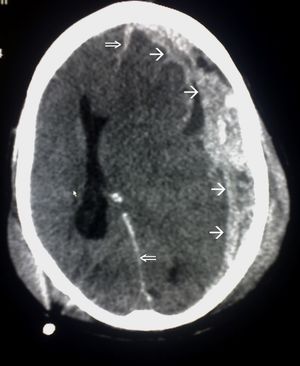

응급 상황에서는 컴퓨터 단층촬영(CT)이 가장 선호되는 방사선 검사다. 신속하고 정확하며 널리 사용 가능하기 때문이다.[73] 손상이 진행되었는지 확인하기 위해 추후 CT 촬영을 실시할 수도 있다.[193]

자기공명영상(MRI)은 CT보다 더 자세한 정보를 보여주며 장기적인 예후에 대한 정보를 추가할 수 있다.[162] 특히 확산성 축삭 손상과 같은 손상 특징을 감지하는 데 CT보다 유용하다.[193] 하지만 MRI는 응급 상황에서는 출혈 및 골절 감지의 상대적 비효율성, 영상 획득 시간이 길다는 점, 기계 내 환자의 접근성 문제, 응급 치료에 사용되는 금속 물체와의 비호환성 등의 이유로 잘 사용되지 않는다.[162] 2012년 이후 MRI의 변형 기술로 고해상도 섬유 추적(HDFT)이 있다.[72]